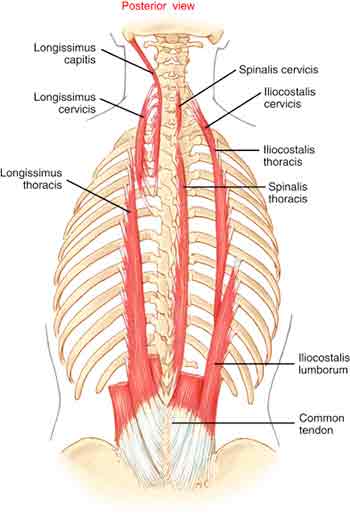

Back pain often means more than just giving you a pain in the back. It can create difficulties with walking, sitting, bending and lifting and can even lead to depression and breathing difficulties. It can also be the cause of pain in the buttocks, groin and legs, sciatica is a good example.

Back pain often means more than just giving you a pain in the back. It can create difficulties with walking, sitting, bending and lifting and can even lead to depression and breathing difficulties. It can also be the cause of pain in the buttocks, groin and legs, sciatica is a good example.Over 2.8 million adults in the UK of all ages suffer from long term back pain, enduring months and years of discomfort.

Acute pain arises suddenly and is most often due to muscle strain. Usually the spine is pulled out of line and mobility is severely restricted.

The muscles governing the movement in the painful area may have been in a hypertense state for years and have just had their 'last straw' placed on them. A nerve can be 'pinched' but more usually they become compressed due to swelling and/or muscle compression around the nerve roots. Usually there is an area of primary trauma with a secondary spread of pain, aching and stiffness which radiates outwards, upwards and downwards, thereby compounding the problem.

A case which illustrates a typical history is one of a young man in his late thirties who had been suffering from a persistent pain in his mid-ribcage on the right for many years. He worked at a computer for long hours every day. He had scans and had been to many doctors, massagists, Osteopaths and Chiropractors in search of an answer to his pain.

I found hypertonus in the muscles in the area of pain. His overall structure was slightly asymmetrical. He also suffered from an intermittent pain in his left front ribcage. Both this and the mid-back pain in his perception seemed to be aggravated by his digestive problems.

I gave him treatment to all the afflicted areas including the stomach and the pain disappeared. Some follow up sessions have maintained this marked improvement.

Conclusion: many long term problems can be resolved quite quickly given the right diagnosis and treatment.